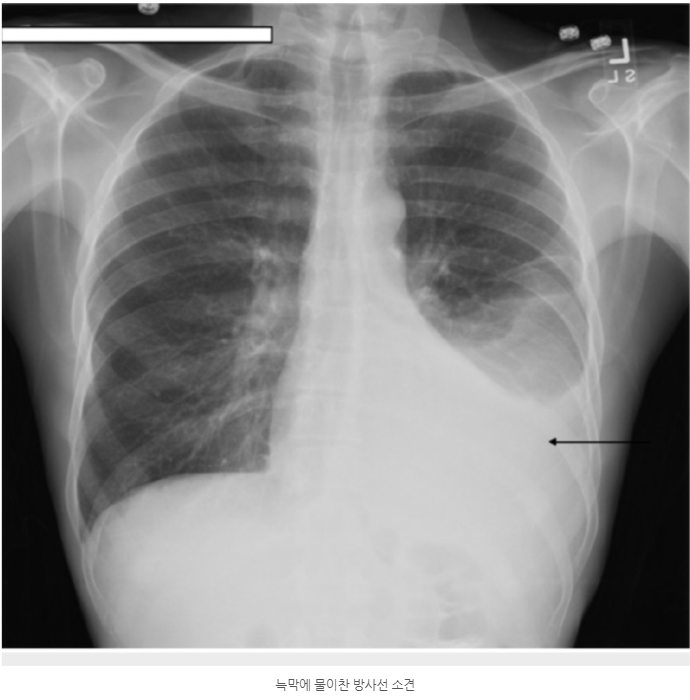

일반적으로 늑막염이라고 하면 여러 가지 원인에 의해서 늑막에 염증이 생기는 것을 말하는데, 이 염증으로 인해서 통증을 일으키고 분비물이 생기면서 늑막강 내에 고여서 흉수가 된다는군요. 흔히 늑막에 물이 고였다고 표현하는 것이 바로 늑막염의 대표적인 증상이라네요.

대부분의 늑막염 증상이라면, 일단 미열과 함께 흉통이 발생하는 것으로 심호흡과 기침으로 악화되어 호흡곤란을 느끼게 된다는 겁니다. 흉통증의 형태는 칼로 찌르는 듯한 날카로운 통증을 나타내기도 한다네요. 무엇보다 전신의 쇠약감이 바로 늑막염 증상의 특징이라는군요.